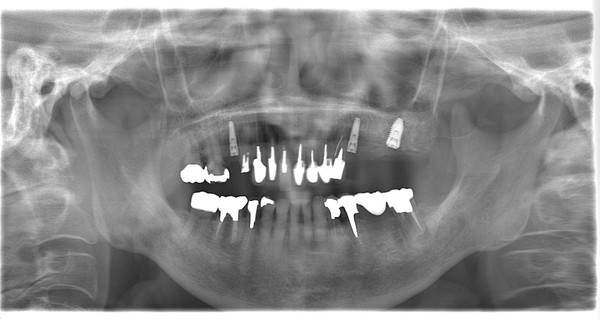

2ケース目は、80歳の女性です。

<術前>

<術後>

オペも楽に終わって、3ヶ月後に仮歯が入るのを楽しみにされていました。